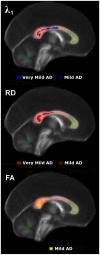

Methods: The biomarker question was addressed in this study by adopting a standardised protocol both for the whole brain (tract-based spatial statistics), and for a region of interest: the midline corpus callosum. In order to study the evolution of tensor changes, cross-sectional data from very mild (N = 21) and mild (N = 22) Alzheimer's disease patients were examined as well as a longitudinal cohort (N = 16) that had been rescanned at 12 months.

Findings and significance: The results revealed that increased axial and mean diffusivity are the first abnormalities to occur and that the first region to develop such significant differences was mesial parietal/splenial white matter; these metrics, however, remained relatively static with advancing disease indicating they are suitable as 'state-specific' markers. In contrast, increased radial diffusivity, and therefore decreased fractional anisotropy-though less detectable early-became increasingly abnormal with disease progression, and, in the splenium of the corpus callosum, correlated significantly with dementia severity; these metrics therefore appear 'stage-specific' and would be ideal for monitoring disease progression. In addition, the cross-sectional and longitudinal analyses showed that the progressive abnormalities in radial diffusivity and fractional anisotropy always occurred in areas that had first shown an increase in axial and mean diffusivity. Given that the former two metrics correlate with dementia severity, but the latter two did not, it would appear that increased axial diffusivity represents an upstream event that precedes neuronal loss.